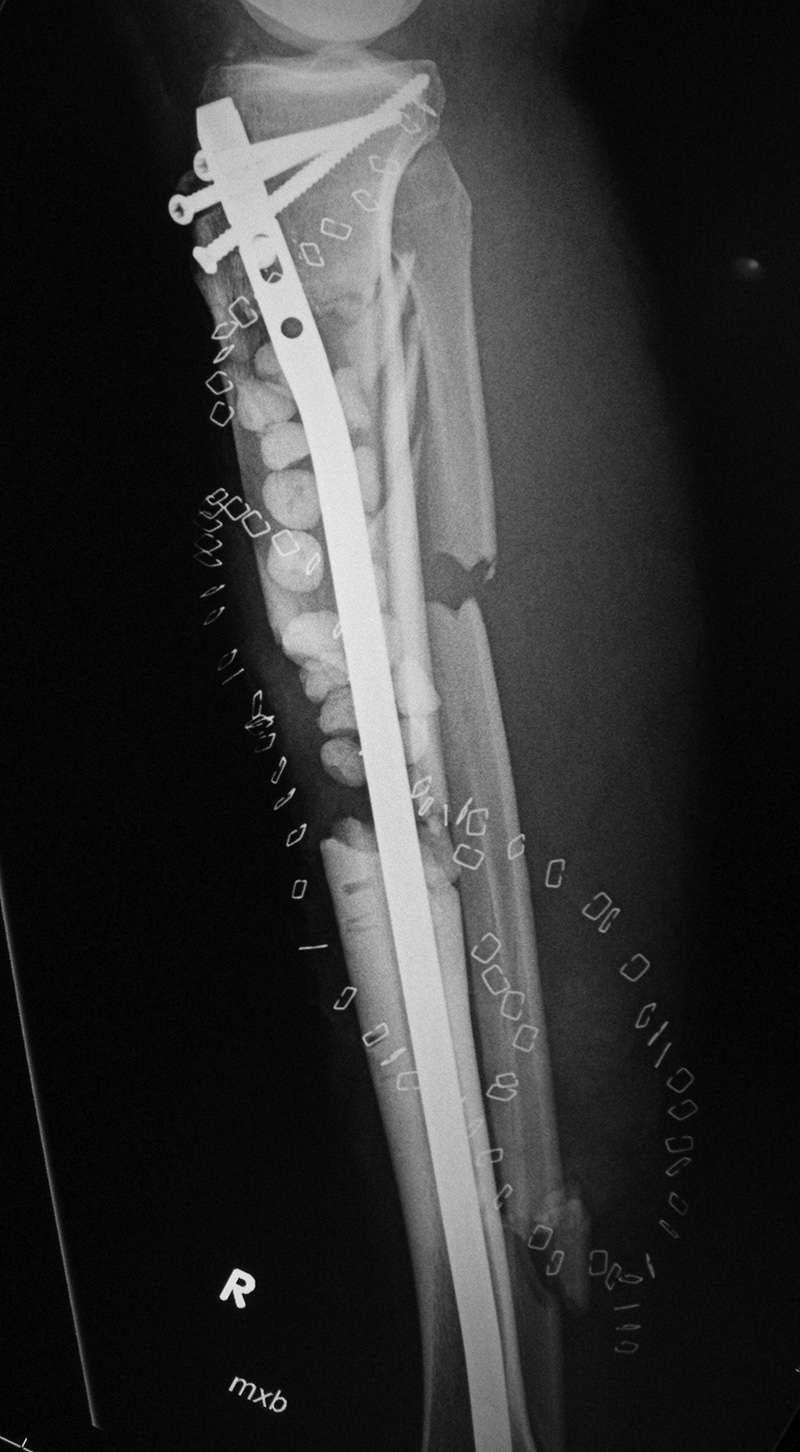

Right tibia bone graft

43 year-old man with comminuted right tibia and fibula fractures as well as extensive bone loss and soft tissue injury. A tibial intramedullary nail with proximal and distal locking screws is present as well as multiple rounded bony allografts. There are also large skin staples.